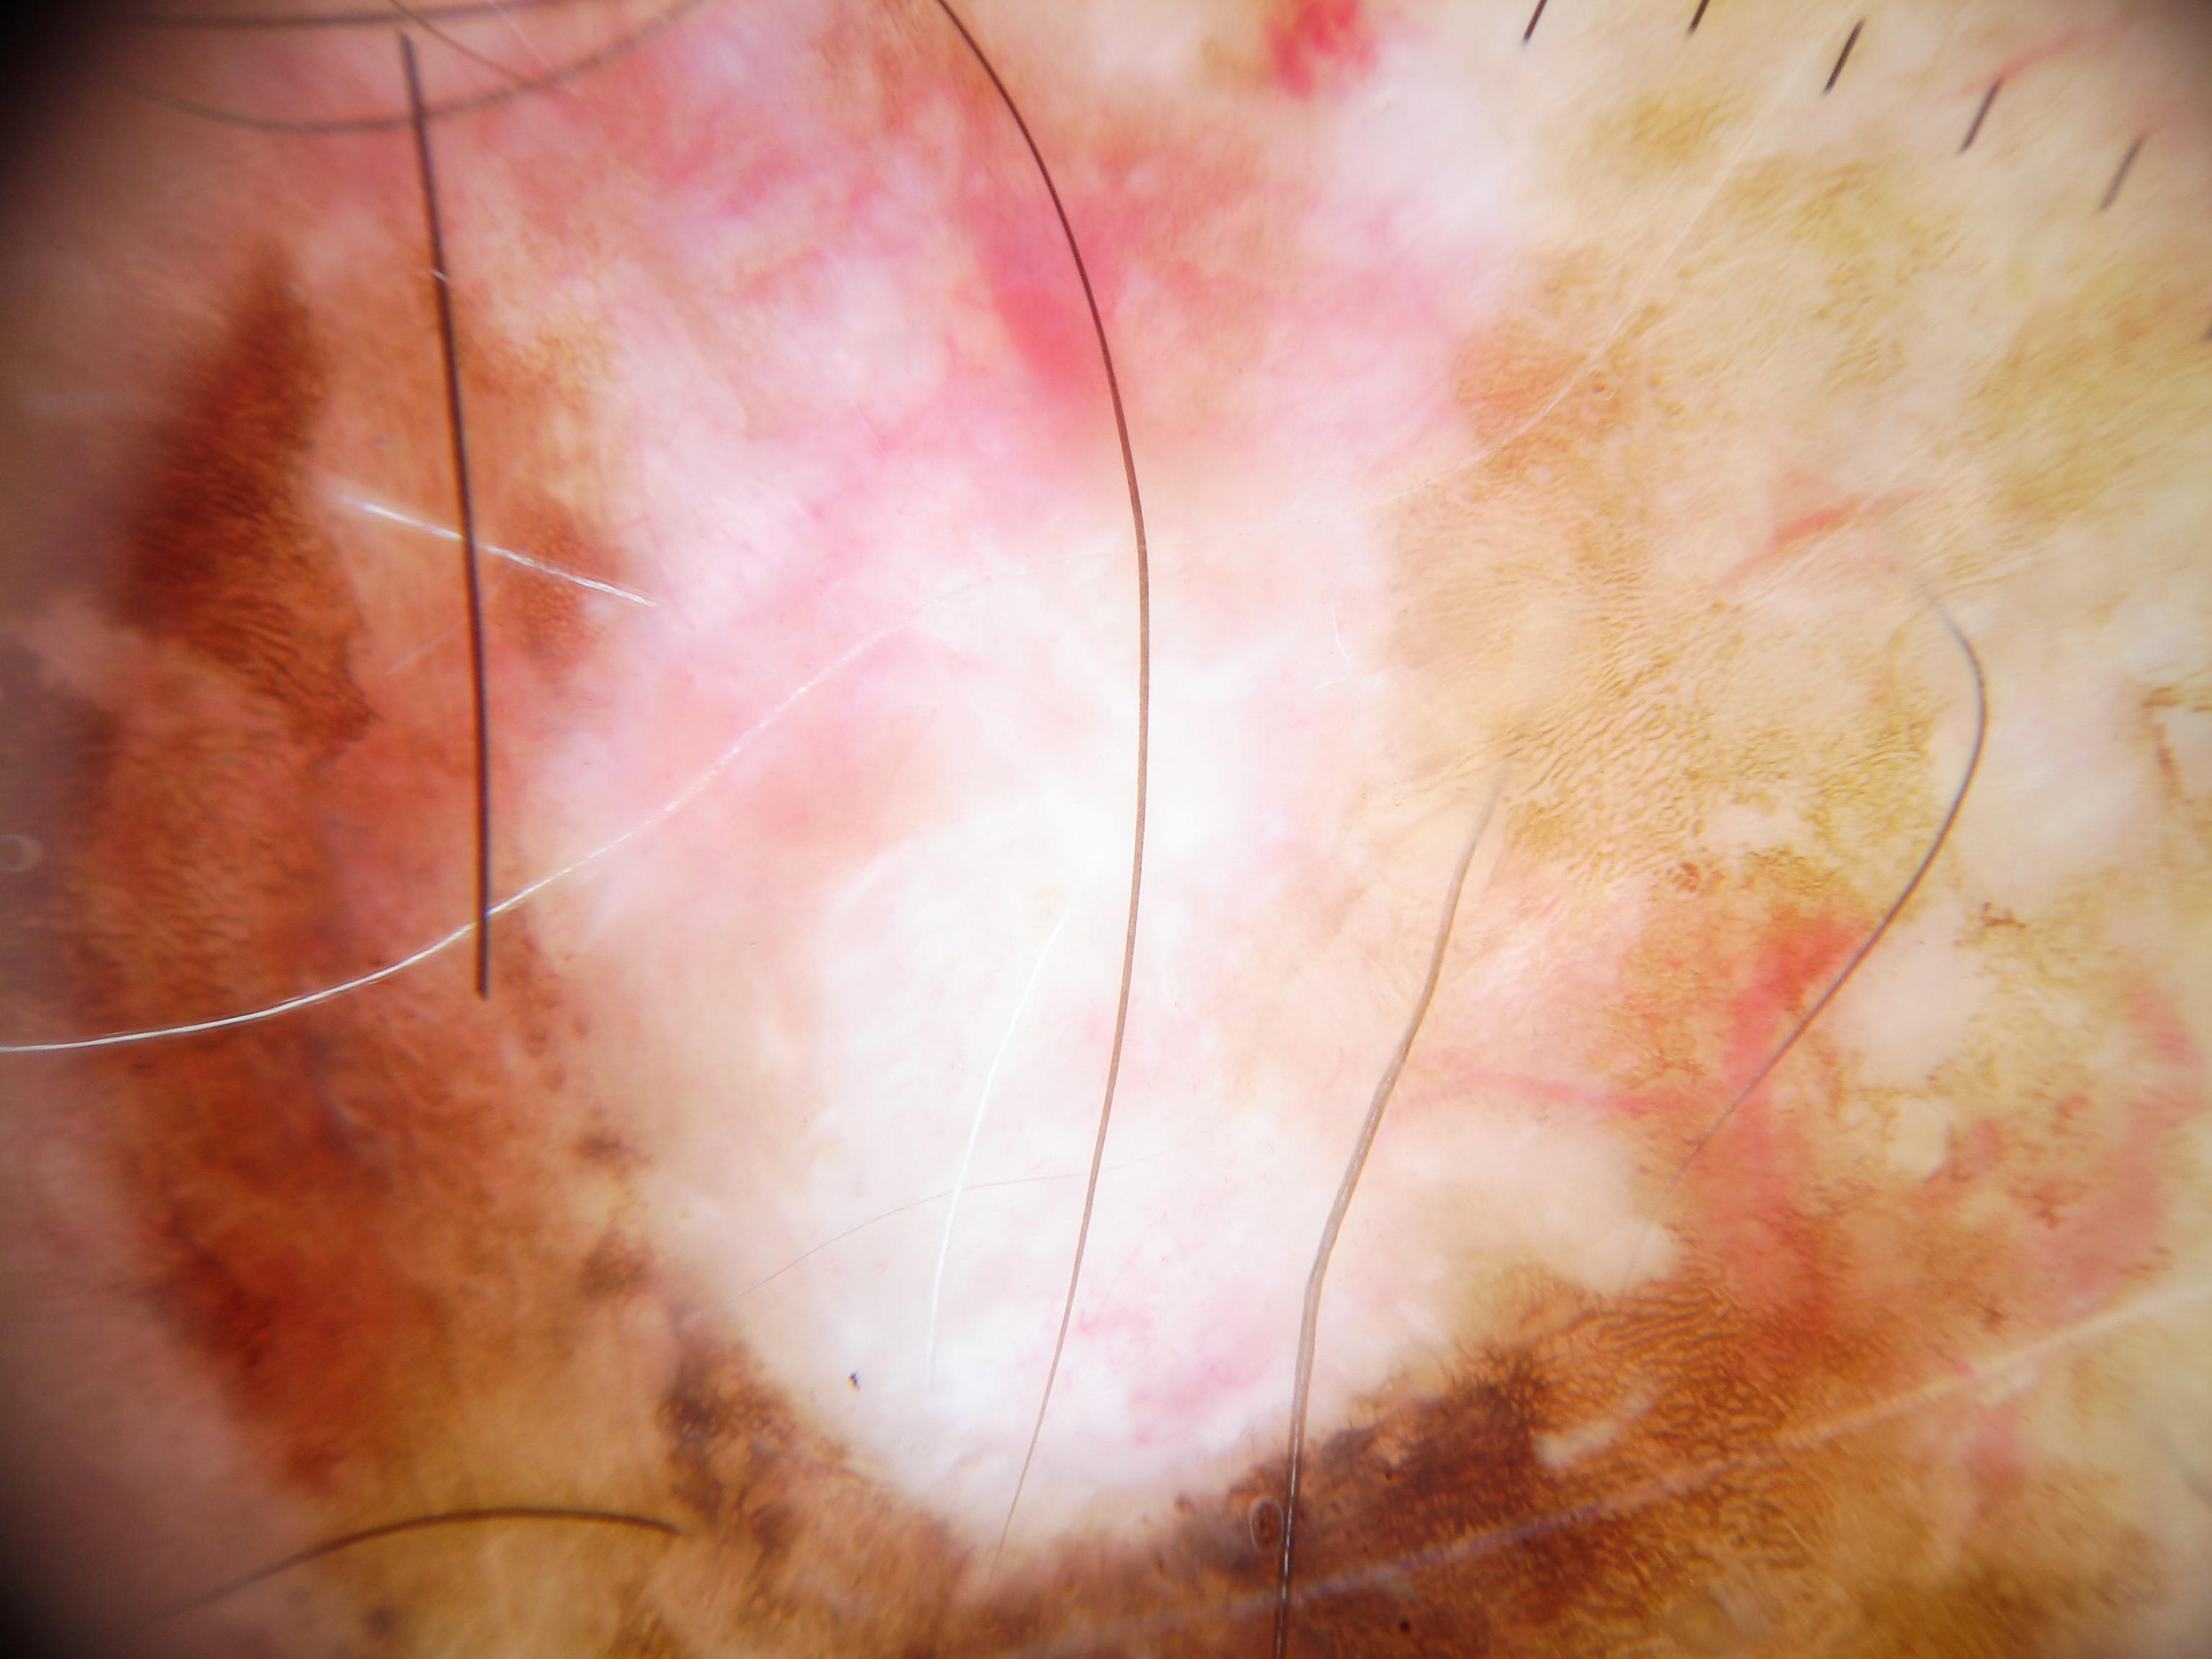

{

"age_approx": 55,

"anatom_site_general": "head/neck",

"concomitant_biopsy": true,

"dermoscopic_type": "non-contact polarized",

"diagnosis_1": "Malignant",

"diagnosis_2": "Malignant adnexal epithelial proliferations - Follicular",

"diagnosis_3": "Basal cell carcinoma",

"diagnosis_confirm_type": "histopathology",

"family_hx_mm": false,

"image_type": "dermoscopic",

"melanocytic": false,

"patient_id": "IP_9463066",

"personal_hx_mm": false,

"sex": "female"